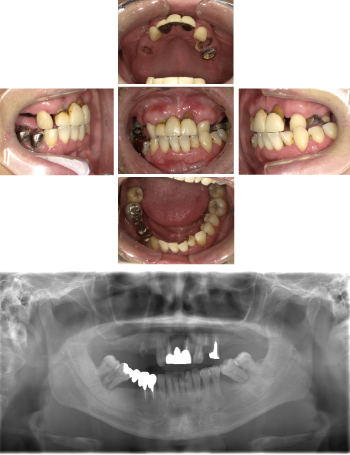

50代 女性 インプラント治療(GBR・ソケットリフト)

| 年代・性別 | 50代・女性 |

|---|---|

| 主訴 | Brの歯が取れそうなため、インプラントに変えたい。 |

| 部位 | 左下567 左上④5⑥ 右上67 |

| 治療期間 | 約3年9ヶ月 |

| 費用 | ¥3,224,500(税込) |

| 副作用・リスク |

|